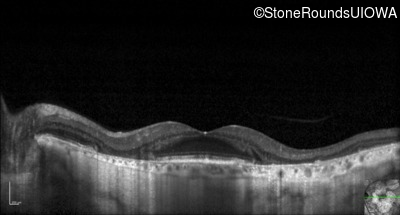

Optical Coherence Tomography - Left - 20/40 +1

Exemplar / OCT Stack

OCT Stack